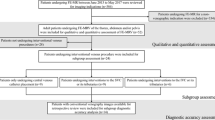

The medical records and imaging data sets of patients who underwent high-resolution 3-D gadofosveset-enhanced MR venography (GE-MRV) or ferumoxytol-enhanced MR venography (FE-MRV) were retrospectively reviewed. Two groups of 20 pediatric patients (age- and weight-matched with one patient common to both groups; age range: 2 days–15 years) who underwent high-resolution 3-D GE-MRV or FE-MRV at similar molar doses were identified and analyzed. Qualitative analysis of image quality and vessel definition was performed by two blinded pediatric radiologists. Interobserver agreement was assessed with the AC1 (first-order agreement coefficient) statistic. Signal-to-noise ratio (SNR) and CNR of the inferior vena cava and aorta were measured in the steady-state venous phase. Medical records were retrospectively reviewed for any adverse reactions associated with either contrast agent.

This study was approved by the local institutional review board and was compliant with the Health Insurance Portability and Accountability Act. The medical records and imaging data sets of patients who underwent high-resolution three-dimensional (3-D) gadofosveset-enhanced MR venography (GE-MRV) or ferumoxytol-enhanced MR venography (FE-MRV) were retrospectively reviewed.

Two groups of 20 pediatric patients (age- and weight-matched with one patient common to both groups; age range: 2 days–15 years) who underwent high-resolution 3-D GE-MRV or FE-MRV at similar molar doses were identified and analyzed.

Qualitative image analysis

The veins were divided into 18 segments: internal jugular veins, subclavian veins, innominate veins, superior vena cava (SVC), superior pulmonary veins, inferior pulmonary veins, tributaries of the superior and inferior pulmonary veins, inferior vena cava (IVC), azygos vein, common iliac veins, external iliac veins, internal iliac veins, superior mesenteric vein, tributaries of the superior mesenteric vein, inferior mesenteric vein, middle hepatic vein, splenic vein, and portal vein. Vascular image quality was evaluated on a 4-point scale as previously described [16] and detailed in Online Supplementary Material 1. In addition, the images were assessed for overall image quality on a 4-point scale (Online Supplementary Material 1).

Quantitative image analysis

Statistical analysis

Continuous data are presented as means and standard deviations, and categorical data are presented as absolute values with frequencies. Normality was tested with the Shapiro–Wilk test. Qualitative and quantitative differences were compared with paired two-tailed t-tests or Wilcoxon rank sum tests as appropriate. Interobserver agreement was assessed with the AC1 (first-order agreement coefficient) statistic in place of Cohen’s kappa value because “kappa’s paradox” was present [18]. AC1 values of < 0.20, 0.21–0.40, 0.41–0.60, 0.61–0.80 and 0.81–1.00 correspond to poor, fair, moderate, good and excellent agreement, respectively. Statistical analysis was performed with SPSS software (version 26.0; IBM, Armonk, NY).